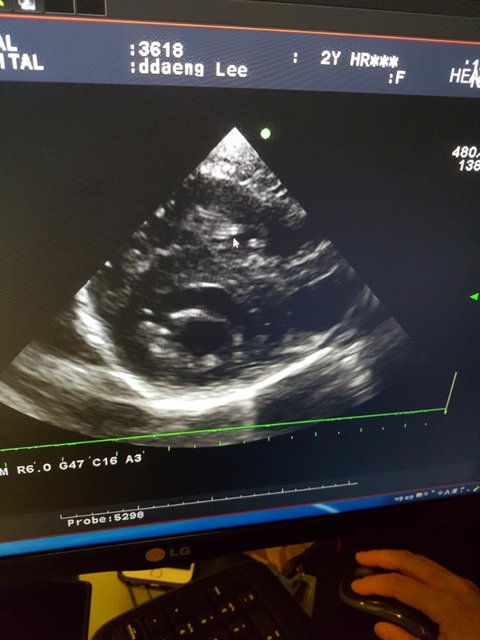

심장사상충..

그것도 너무나 많은 자충과 성충들이 온몸에 퍼져있다고 합니다.

보기드물게 폐에까지 성충이 자리잡고 있다고 합니다.